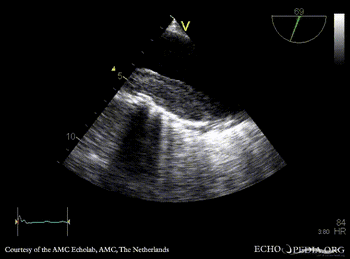

| TEE: dilated aorta | TEE: intramural hematoma of aorta |

| TEE: intramural hematoma of aorta | |